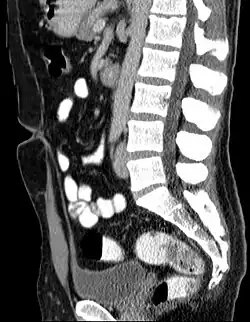

L’ouraque est un cordon fibreux joignant le pôle antéro-supérieur de la vessie à l'ombilic.

L'ouraque est un cordon fibreux creux mais borgne (fermeture physiologique des deux extrémités) présent dans l'abdomen, chez l'humain, et reliant la vessie à l'ombilic. C'est le vestige du canal allantoïdien, qui relie chez l'embryon le cloaque au cordon ombilical, et qui régresse à partir de la 6e semaine ; sa fermeture est normalement complète à la naissance.